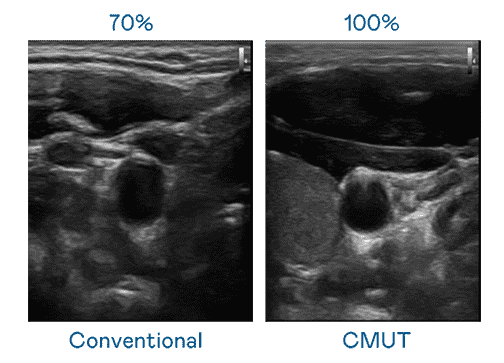

CMUT 技术是一种用电容式微机电元件来产生超音波讯号的技术。。与传统 PZT 压电式技术相比,,,CMUT 频宽增加 30%,,更宽频的超音波讯号让影像解析度大幅提升,,,是实现高影像品质医疗超音波扫描、、、促进精准医疗发展的关键技术。。

大频宽带来超清晰影像

超音波影像的解析度高低,,,首先取决于探头能发出的讯号频宽。。。。银河集团 CMUT 可提供高清晰的超音波讯号,,,提供高频宽、、、、高灵敏度、、、、影像纹理细节更高的超音波影像,,,,协助医护人员缩短影像判读时间及利用精准的医疗影像进行诊断。。。